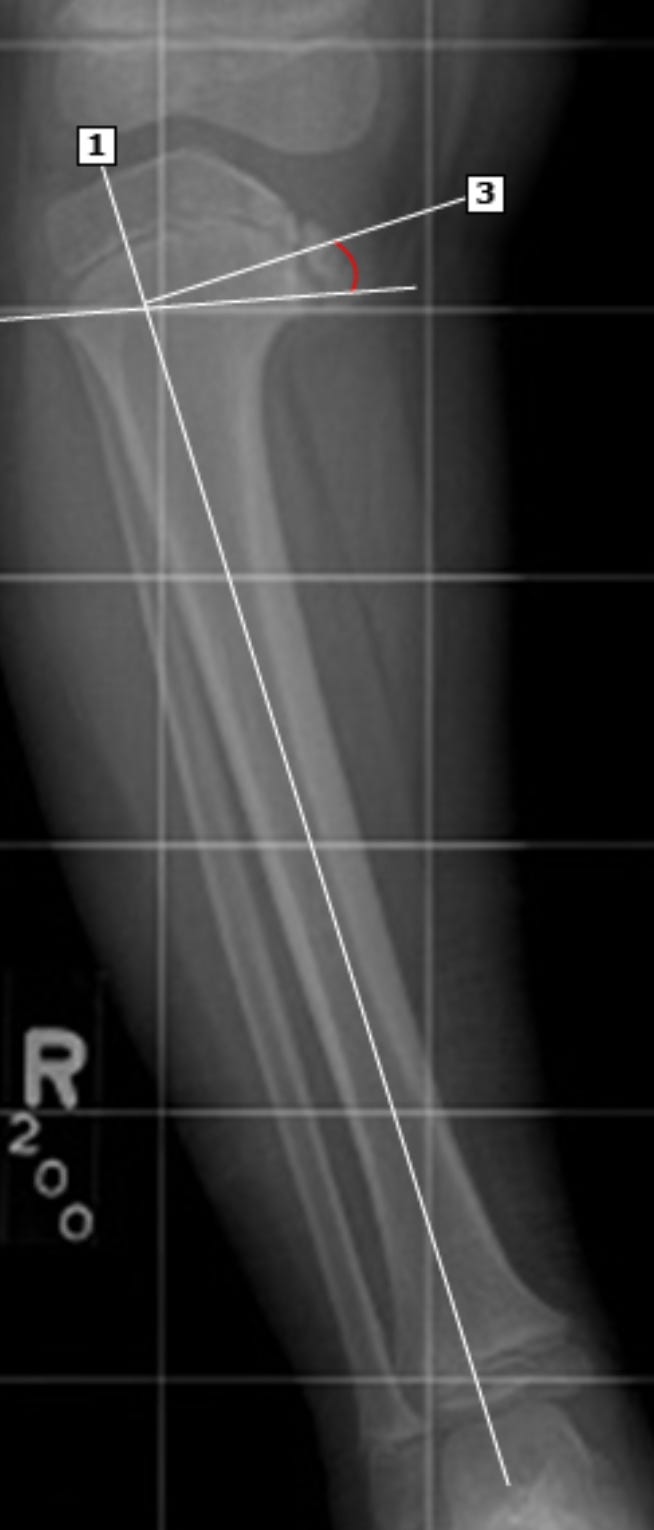

Угол между метадиафизарный угол измеряется на переднезаднем рентгеновском снимке коленного сустава в положении стоя следующим образом: 1) проводится линия вдоль продольной оси большеберцовой кости (линия 1); 2) проводится линия через вершины проксимального метафиза большеберцовой кости (линия 2); 3) проводится линия, перпендикулярная линии 1, в точке пересечения линий 1 и 2 (линия 3); 4) измеряется угол между линиями 2 и 3 — это и есть угол между метафизом и диафизом большеберцовой кости. Значение угла ≤11° указывает на физиологическую, а не патологическую О-образную деформацию. У этого пациента с болезнью Блаунта метадиафизарный угол равен примерно 18°.

Метафизарно-диафизарные (МД) углы:

Цель: определение локализации и относительной тяжести деформации

Техника измерения: угол между линией, проведенной через метафиз, и линией, проведенной через диафиз кости

Большеберцовый МД угол >16°: предполагает болезнь Блаунта

Соотношение бедренный МД угол : большеберцовый МД угол:

>1: предполагает физиологическое искривление

<1: предполагает болезнь Блаунта